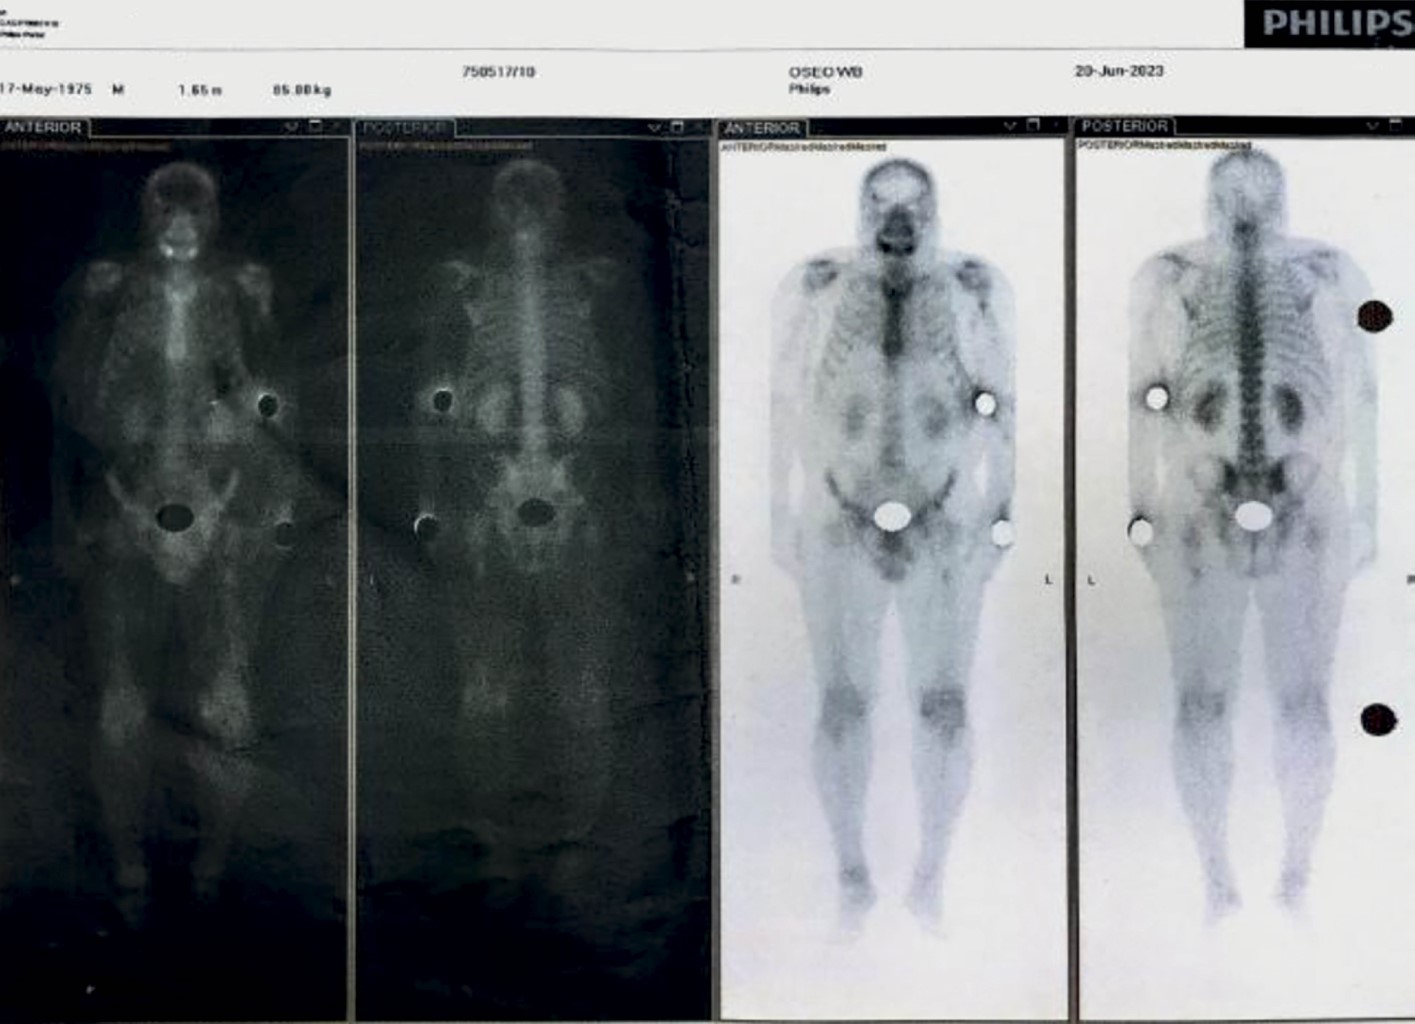

Posteriormente se realiza gammagrama MDP 99mTc con fecha 20/Junio/2023. Descripción: dos horas después de la administración por vía intravenosa en miembro torácico de una dosis de difosfonato de metileno (MDP) marcado con 20 mCi de 99mTc, se adquiere rastreo corporal en proyecciones anterior y posterior en donde se observa: Fase dinámica: paso del radiotrazador a través de grandes vasos, subclavia y carótida de forma simétrica y simultánea Fase inmediata: incremento de la concentración en tejidos blandos en región mandibular derecha. Fase tardía (ósea): existe incremento de la captación en rama mandibular derecha y como conclusión el incremento osteoblástico referido está en relación con evento postquirúrgico (biopsia) y negativo para actividad infiltrativa en el esqueleto axial y apendicular (Figuras 9 y 10).

Diagnóstico. Para un correcto diagnóstico, se evalúan datos clínicos, radiográficos e histológicos. Se debe tener enfoque multidisciplinario, que incluya un examen clínico en profundidad, pruebas complementarias como hemograma completo, recuento de plaquetas, pruebas de coagulación, función hepática, bioquímica de orina y pruebas BRAF V600E. Además, algunos estudios de imágenes, como radiografías, resonancia magnética, ecografía, gammagrafía ósea y TAC.3,17